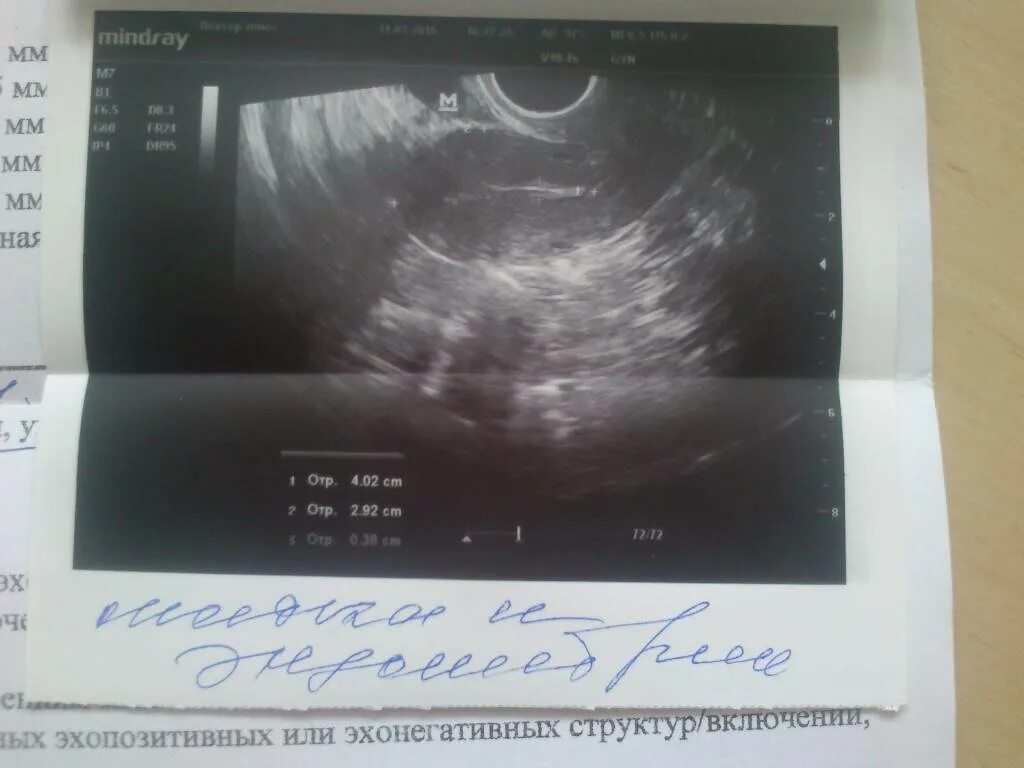

Можно ли забеременеть при загибе матки